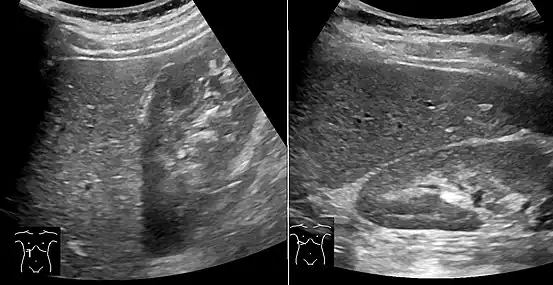

On X-ray computed tomography (CT), the increased fat component will decrease the density of the liver tissue, making the image less bright. Typically the density of the spleen and liver are roughly equivalent. In steatosis, there is a difference between the density and brightness of the two organs, with the liver appearing darker.[12] On ultrasound, fat is more echogenic (capable of reflecting sound waves). The combination of liver steatosis being dark on CT and bright on ultrasound is sometimes known as the flip flop sign.

On abdominal ultrasonography, steatosis is seen as a hyperechoic liver as compared to the normal kidney.

Abdominal ultrasonography with the liver and kidney side by side (left image) may give a false impression of hyperechogenic liver, so it's preferably done with the organ borders facing the ultrasound probe (right image, of the same case).